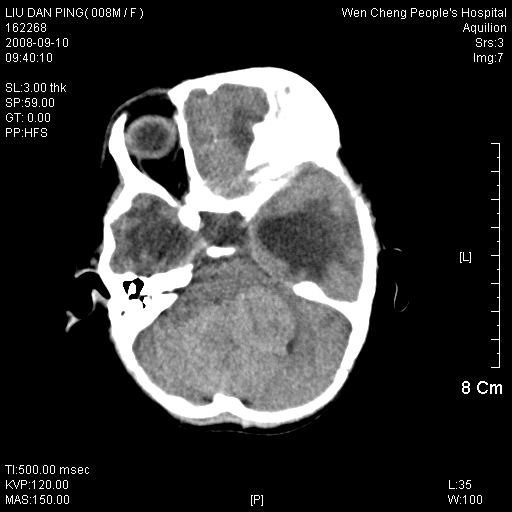

以下是引用卜一在2008-9-10 16:21:00的发言:[br]髓母细胞瘤伴梗阻性脑积水!支持![br]髓母细胞瘤特点:—般直径大于3.5cm,位于后颅凹中线之小脑蚓部。累及上蚓部的肿瘤延伸到小脑幕切迹之上,ct平扫肿瘤多呈均匀一致的高或等密度病灶,增强检查呈均匀一致的强化。病灶中有小坏死时,平扫亦可呈不均匀之混杂密度,注药后有增强。[br]

以下是引用zjzjr在2008-9-10 15:09:00的发言:[br]髓母细胞瘤伴梗阻性脑积水.